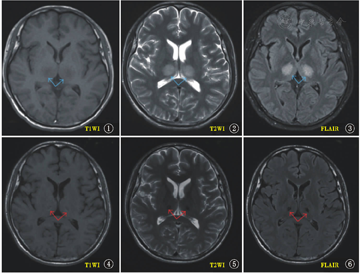

图8、图9为一轻型ANE病例的ADC图[22](缺少典型病例的A表现),表现为中央ADC值低(为细胞毒性水肿),而在DWI呈高信号(因弥散受限),其周围的ADC值高(表示血管源性水肿),而在DWI呈等信号(因弥散不受限)。而图10、图11为2个月后慢性期的ADC和DWI,异常信号消失,仅存有较小的囊腔(含铁血黄素沉积后)表现。